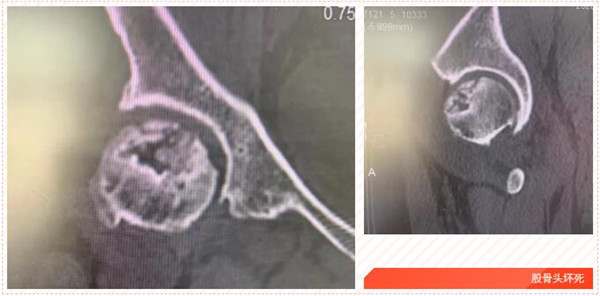

五年前,家住岱山的洪女士發(fā)覺自己的髖部經(jīng)常疼痛,有時候活動都受影響,特別時久行后更是疼痛難忍,便到我市某院就診,經(jīng)檢查診斷為“雙側(cè)股骨頭壞死”,予以口服藥物等保守治療,可并沒有好轉(zhuǎn)。

2017年5月,在朋友的建議下,洪女士來到我院,經(jīng)CT診斷雙側(cè)股骨頭無菌性壞死。便在危立軍副院長的建議下,做了左髖關節(jié)置換術。術后,洪女士恢復良好。